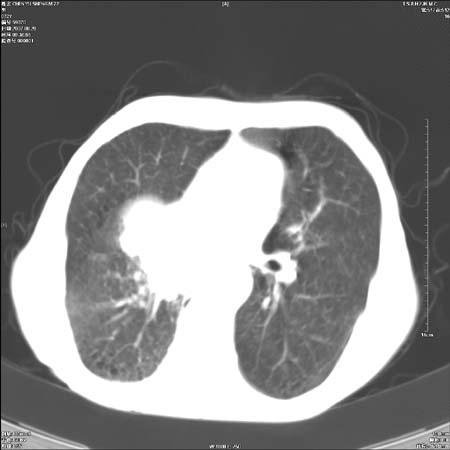

男性,72岁,既往肺结核,今复查。无前片对比。

右侧中央型肺癌伴中叶不张可能性大,建议增强扫描.右上肺陈旧性肺结核.慢性支气管炎伴肺气肿.右侧少量胸腔积液.

右侧中央型肺癌伴中叶不张可能性大,建议纤支镜检查.右上肺陈旧性肺结核.肺气肿。

典型右肺中心型肺癌

右侧中央型肺癌伴肺不张可能性大,建议增强扫描.右上肺陈旧性肺结核.慢性支气管炎伴肺气肿.右侧少量胸腔积液.

右肺中心型肺癌

右侧中央型肺癌.上肺陈旧性肺结核.

1右侧中央型肺癌伴中叶不张2右侧少量胸腔积液3右上肺陈旧性肺结核

1.右肺中心性肺癌并右肺中叶综合征2。右侧胸腔少量积液3。右肺上叶结核球已钙化,4。慢支伴肺气肿

右侧中央型肺癌伴中叶不张可能性大,建议纤支镜检查.右上肺陈旧性肺结核.肺气肿。

右侧中央型肺癌伴中叶不张可能性大,建议增强扫描.右上肺陈旧性肺结核.慢性支气管炎伴肺气肿.右侧少量胸腔积液.

右侧中央型肺癌伴中叶不张

右肺中央型肺癌伴右肺中叶不张。

右上肺陈旧性肺结核。

支持右肺中心型肺癌并中叶不张,右上肺陈旧性肺结核钙化,右侧少量胸腔积液。

支持右侧中央型肺癌伴中叶不张可能性大,建议增强扫描.右上肺陈旧性肺结核.慢性支气管炎伴肺气肿.右侧少量胸腔积液.

支持 1右侧中心型肺癌伴中叶不张2右侧少量胸腔积液3右上肺陈旧性肺结核4双肺局限性肺气肿

1,右侧中央型肺癌.

2,右上肺陈旧性肺结核.

1.右侧中央型肺癌伴中叶不张,建议纤支镜检查.

2.右上肺陈旧性肺结核.

3.肺气肿。

4.右侧少量胸腔积液.

右侧中央型肺癌伴中叶不张并纵隔淋巴结增大,建议增强扫描.右上肺陈旧性肺结核.慢性支气管炎伴肺气肿.右侧少量胸腔积液。

右肺中心型肺癌并肺不张,陈旧性肺tb.慢支,肺气肿.

陈旧性肺结核.慢性支气管炎伴肺气肿,中央型肺癌伴中叶不张。

右侧中央型肺癌伴中叶不张可能性大;右上肺陈旧性肺结核.慢性支气管炎伴肺气肿

陈旧性结核是存在,但真正致命的却是右侧中心型肺癌。